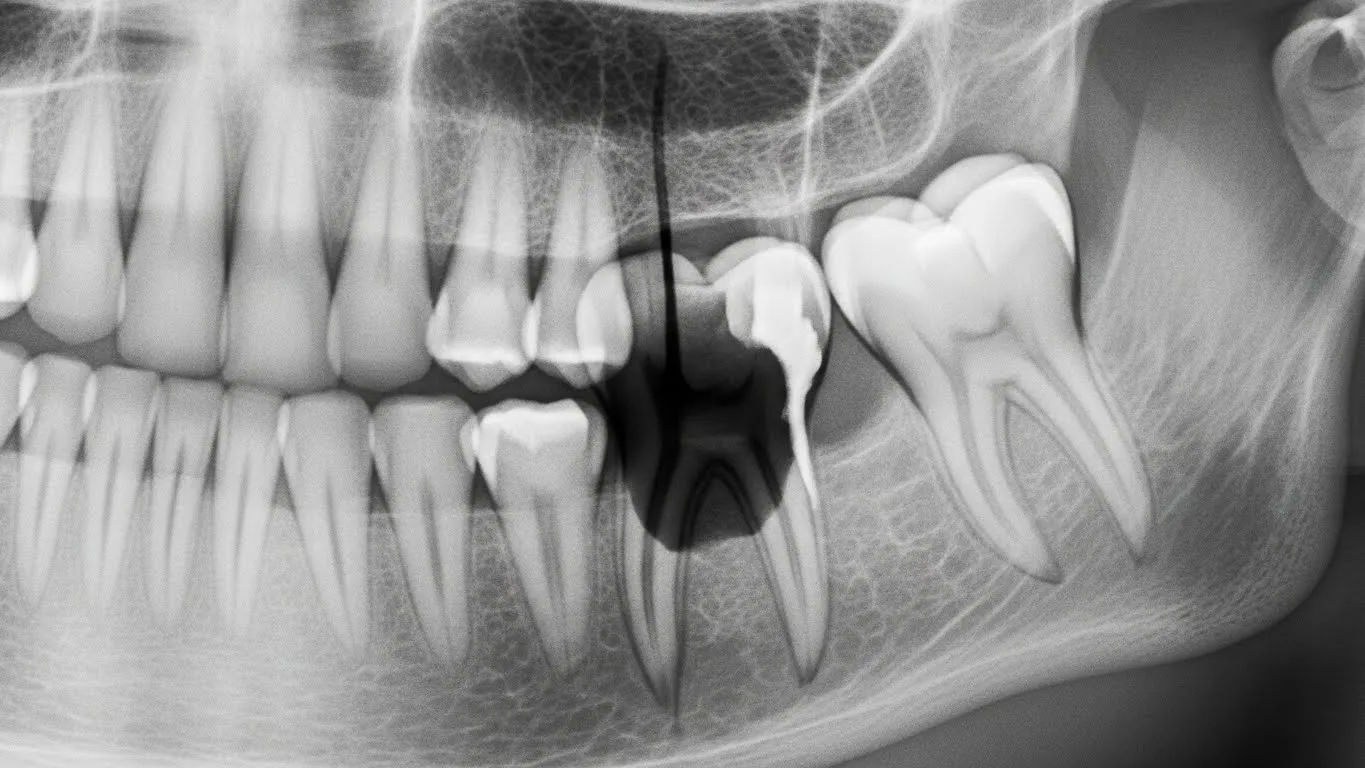

Ah, the great mimics — nature’s little pranksters. Sinusitis (especially maxillary) can cause upper molar pain *indistinguishable* from a periapical abscess — same dull ache, same pressure on bending forward. TMJ disorders? Can refer pain to molars and cause jaw stiffness. Even shingles (pre-eruption!) may burn along the trigeminal nerve like a rogue abscess. Then there’s *cracked tooth syndrome*: sharp pain on release of biting, no visible swelling — easily misread as early abscess. One endodontist chuckled: “I’ve had patients swear it’s an abscess… turned out they’d just chipped a cusp on a Werther’s Original.” So yes — signs of an abscess tooth *overlap*. That’s why diagnosis needs percussion tests, palpation, *and* an X-ray (or CBCT). Don’t trust Google’s algorithm over a radiograph.

Several conditions mimic signs of an abscess tooth: maxillary sinusitis (causes upper molar pain), temporomandibular joint (TMJ) disorders (jaw pain, clicking), cracked tooth syndrome (sharp pain on bite release), trigeminal neuralgia (electric shock-like facial pain), and even cardiac ischaemia (referred jaw pain). Shingles (pre-eruption) can also cause burning unilateral pain. Proper diagnosis requires clinical exam, percussion/palpation tests, and imaging (X-ray/CBCT) to differentiate.